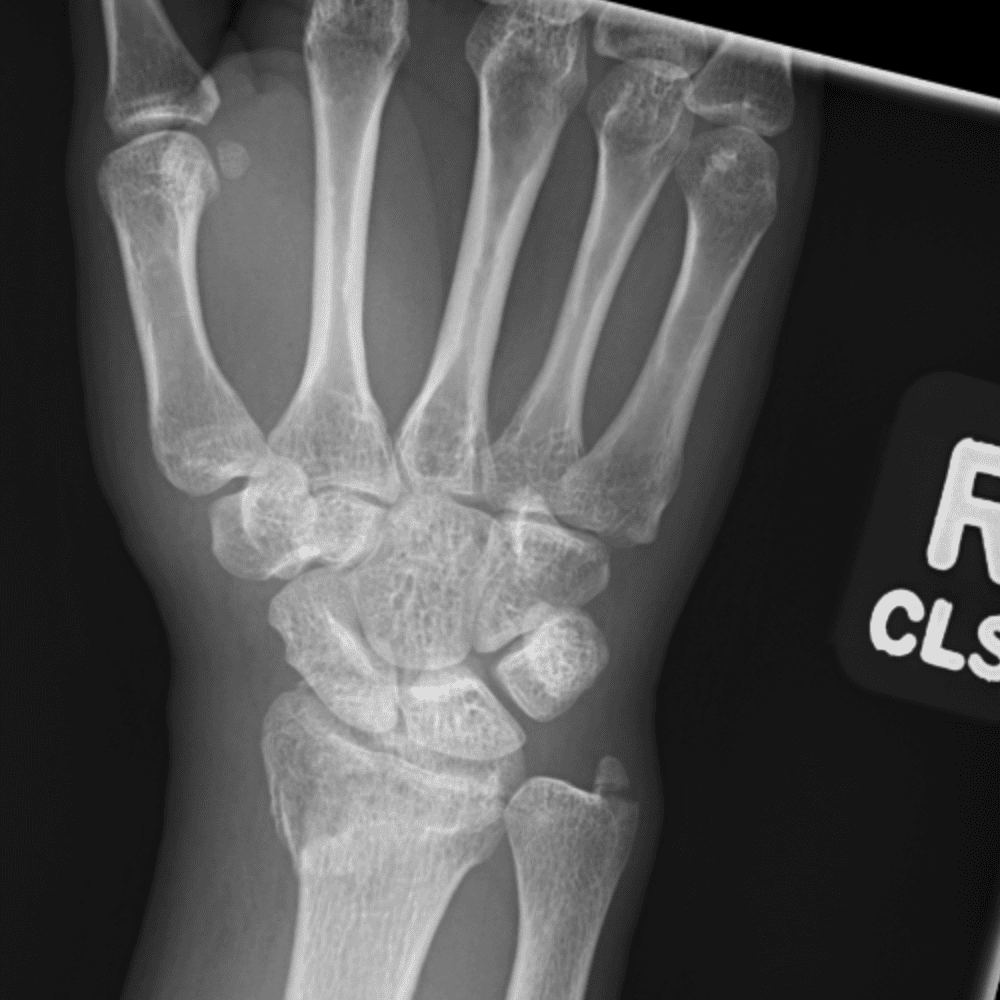

Simuliert den Dienst durch subtile oder schwierige Fälle und einige Normalbefunde.

30 Fälle